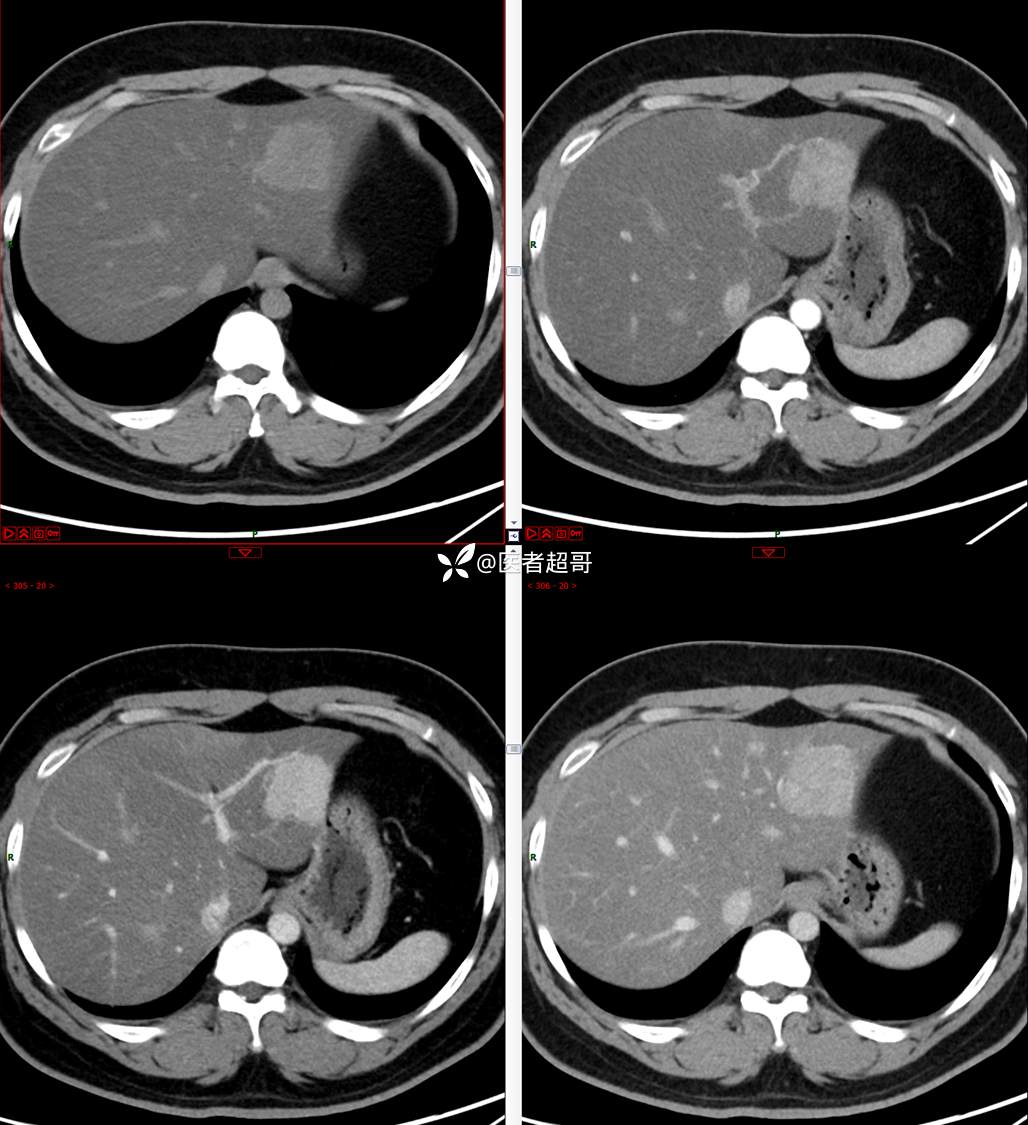

【影诊笔记685】男,31y,发现肝占位性病变5天就诊,请诊断分析,有病理结果!

主 诉:发现肝占位性病变5天。

现病史:患者缘于5天前体检时发现肝占位性病变,未予以特殊处置。现患者为求系统诊治就诊于我院,行普美显提示:肝左叶富血供占位,请结合临床及其他检查,肝多发血管瘤,脂肪肝,肝囊肿,请结合临床。门诊以“肝占位性病变”收入我科。病程中,饮食睡眠可,二便可,近期体重未见明显变化。